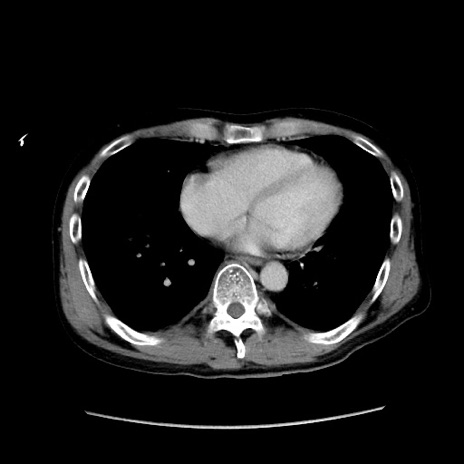

症例37(横断像)

【症例】40歳代 男性

【主訴】腹痛

【現病歴】4時間ほど前に電車に乗車中に臍部上より腹痛出現。徐々に増悪し起立困難となり、救急外来受診。生ものは数日食べていない。今朝お雑煮を食べた。

【身体所見】BT 36.8℃、BP 117/84mmHg、HR 91/min、SpO2 97%、苦悶様、腹部:臍上部広範囲圧痛あり、反跳痛±

【データ】WBC 8100、CRP 0.03